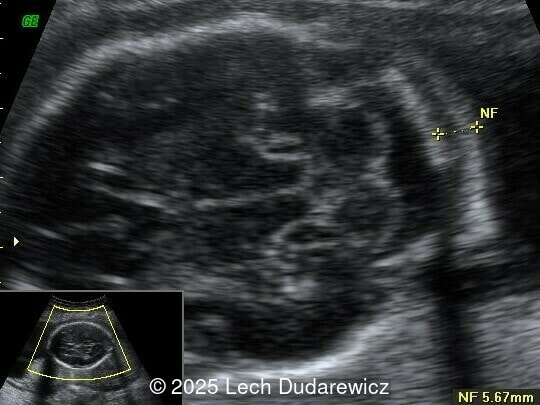

Ultrasound revealed a single live fetus with 46,XY karyotype. Biometric measurements demonstrated discrepancies with the femur and tibia length lagging significantly at 19 weeks and notable shortening and bowing of the femur, tibia, and fibula. The findings were consistent with skeletal dysplasia.

Structural anomalies were observed in multiple organ systems. The fetal skeleton showed hypoplastic iliac bones, rib deformities, hypoplastic scapulae, and excessive cervical spine lordosis. The fetal hands exhibited abnormal alignment of the fingers with restricted movement, and both feet were clubbed. Subcutaneous edema was noted over the forehead and occiput with a small cystic hygroma, along with increased nuchal fold thickness at 5.6mm, indicative of soft tissue edema. Additional abnormalities included mild pyelectasis. The fetal stomach appeared nearly empty, likely reflecting impaired swallowing or associated anomalies. Polyhydramnios was also noted. External male genitalia appeared normal. Cardiac evaluation revealed multiple echogenic foci within the left ventricle and an atrioventricular septal defect. While the heart's overall structure and function were otherwise normal, these findings added to the overall suspicion of a syndromic condition.